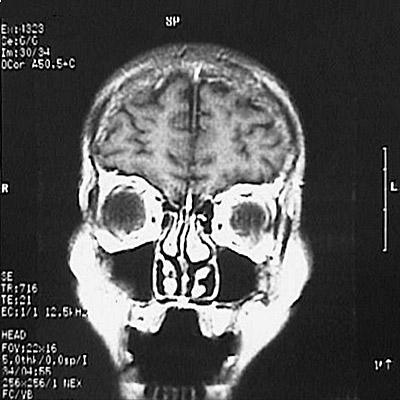

This is a normal coronal T1 weighted enhanced MRI scan demonstrating the frontal lobe and maxillary sinus and nasal cavity and concha and oral cavity and superior sagittal sinus and falx cerebri and orbit.